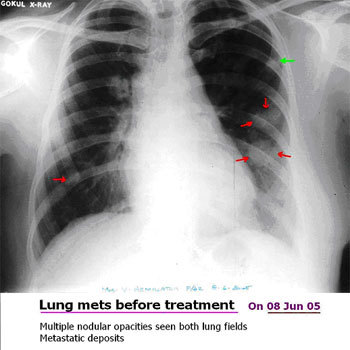

• Cured cancer using Herbal Oncology and proved with PET scans